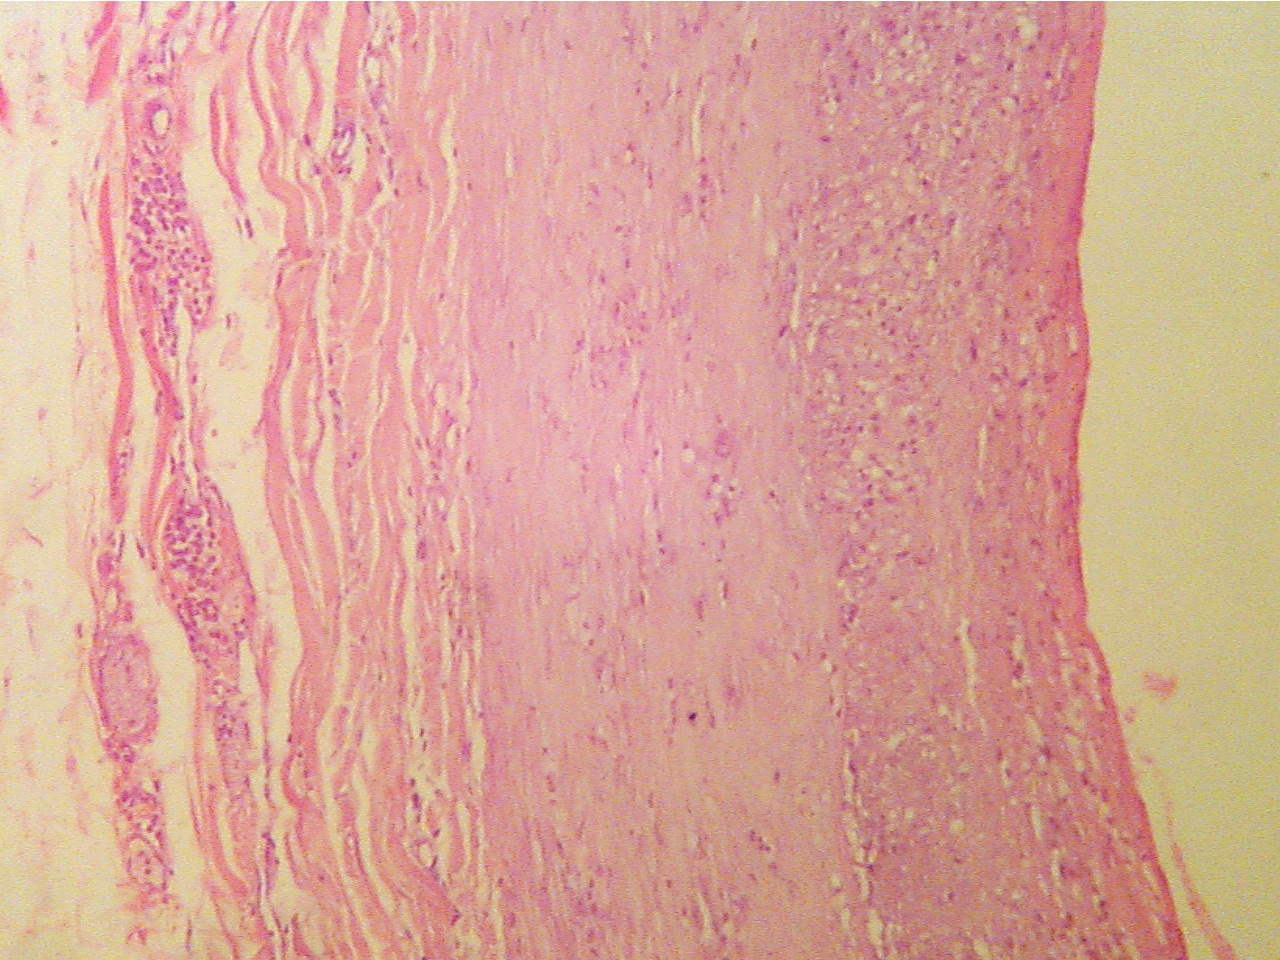

Normal region (100X2.0 - a1)

Early lesion (100X2.0 - a2)

Layers are areolar tissue (left), externa (thick pink

Lumen at upper left, endothelium (thin layer),

collagen fibers),

smooth muscle (thick middle layer),

intima, fibrous plaque within intima, intima (darker

granular

tunica intima (thick granular layer),

endothelium

layer), smooth muscle (thick pink), externa (lower right)

(thin red layer), lumen at

right